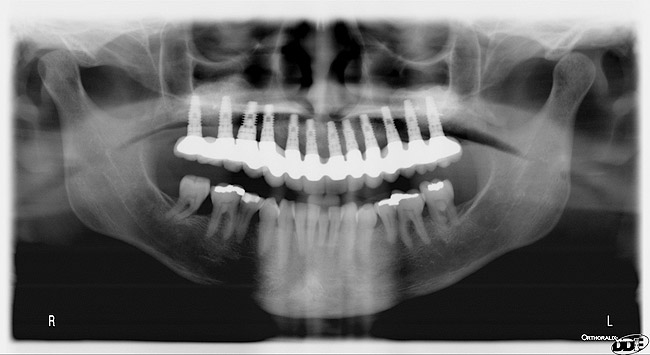

A DFDBA bone-graft putty (Regeneform) was used to graft the entire maxillary arch. All extraction defects were degranulated, the bone was decorticated to allow bleeding, then the DFDBA putty was placed and covered with resorbable collagen membranes (Biomend Extend, Zimmer Dental) (Figure 5). Primary closure was obtained and the patient wore her denture after a soft reline for a period of 6 months (Figure 6). At 6 months post-graft, a CBCT scan revealed substantial graft material from both an axial (Figure 7) and a crosssectional view, showing more than 15 mm of bone height (Figure 8). The 3D view from the CBCT also showed substantial ridge changes in both height and width (Figure 9). Using a CBCT software program (SimPlant, Materialise Dental Inc, Glen Burnie, MD), implants were planned for placement (Figure 10). As per the CBCT plan, 11 internal hex implants (BioHorizons, Birmingham, AL) were placed in the grafted bone (Figure 11). The ideal bone height allowed implant placement in an ideal position with relation to esthetics and occlusion.

Figure 12  Post-placement panographic revealing implant positions.

Figure 12